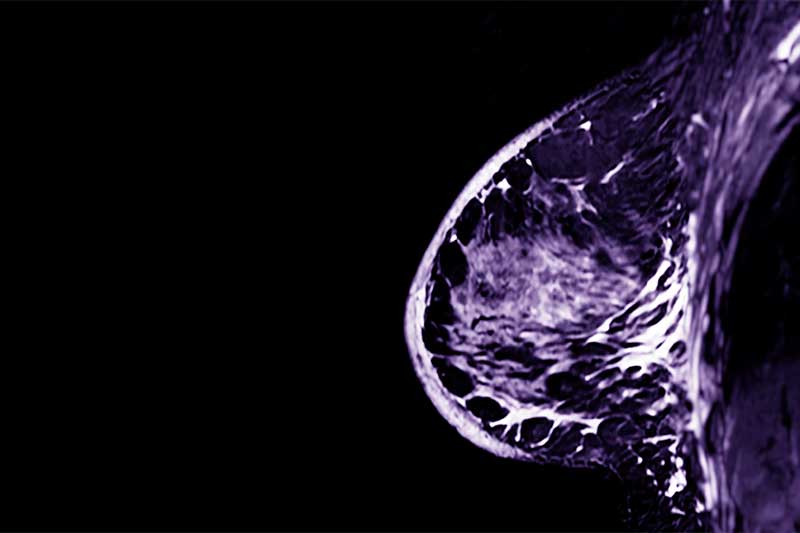

L’ecografia mammaria a Catenanuova impiega sonde ad alta frequenza (≥ 10 MHz), garantendo un’accurata valutazione del tessuto mammario. Questo esame non invasivo è privo di radiazioni ionizzanti, rendendolo sicuro e ripetibile. Viene spesso utilizzato come completamento della mammografia per ottenere una diagnosi più completa e dettagliata.